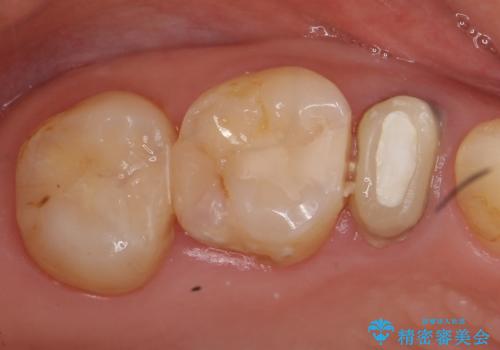

オールセラミッククラウン 根管治療 奥歯の補綴